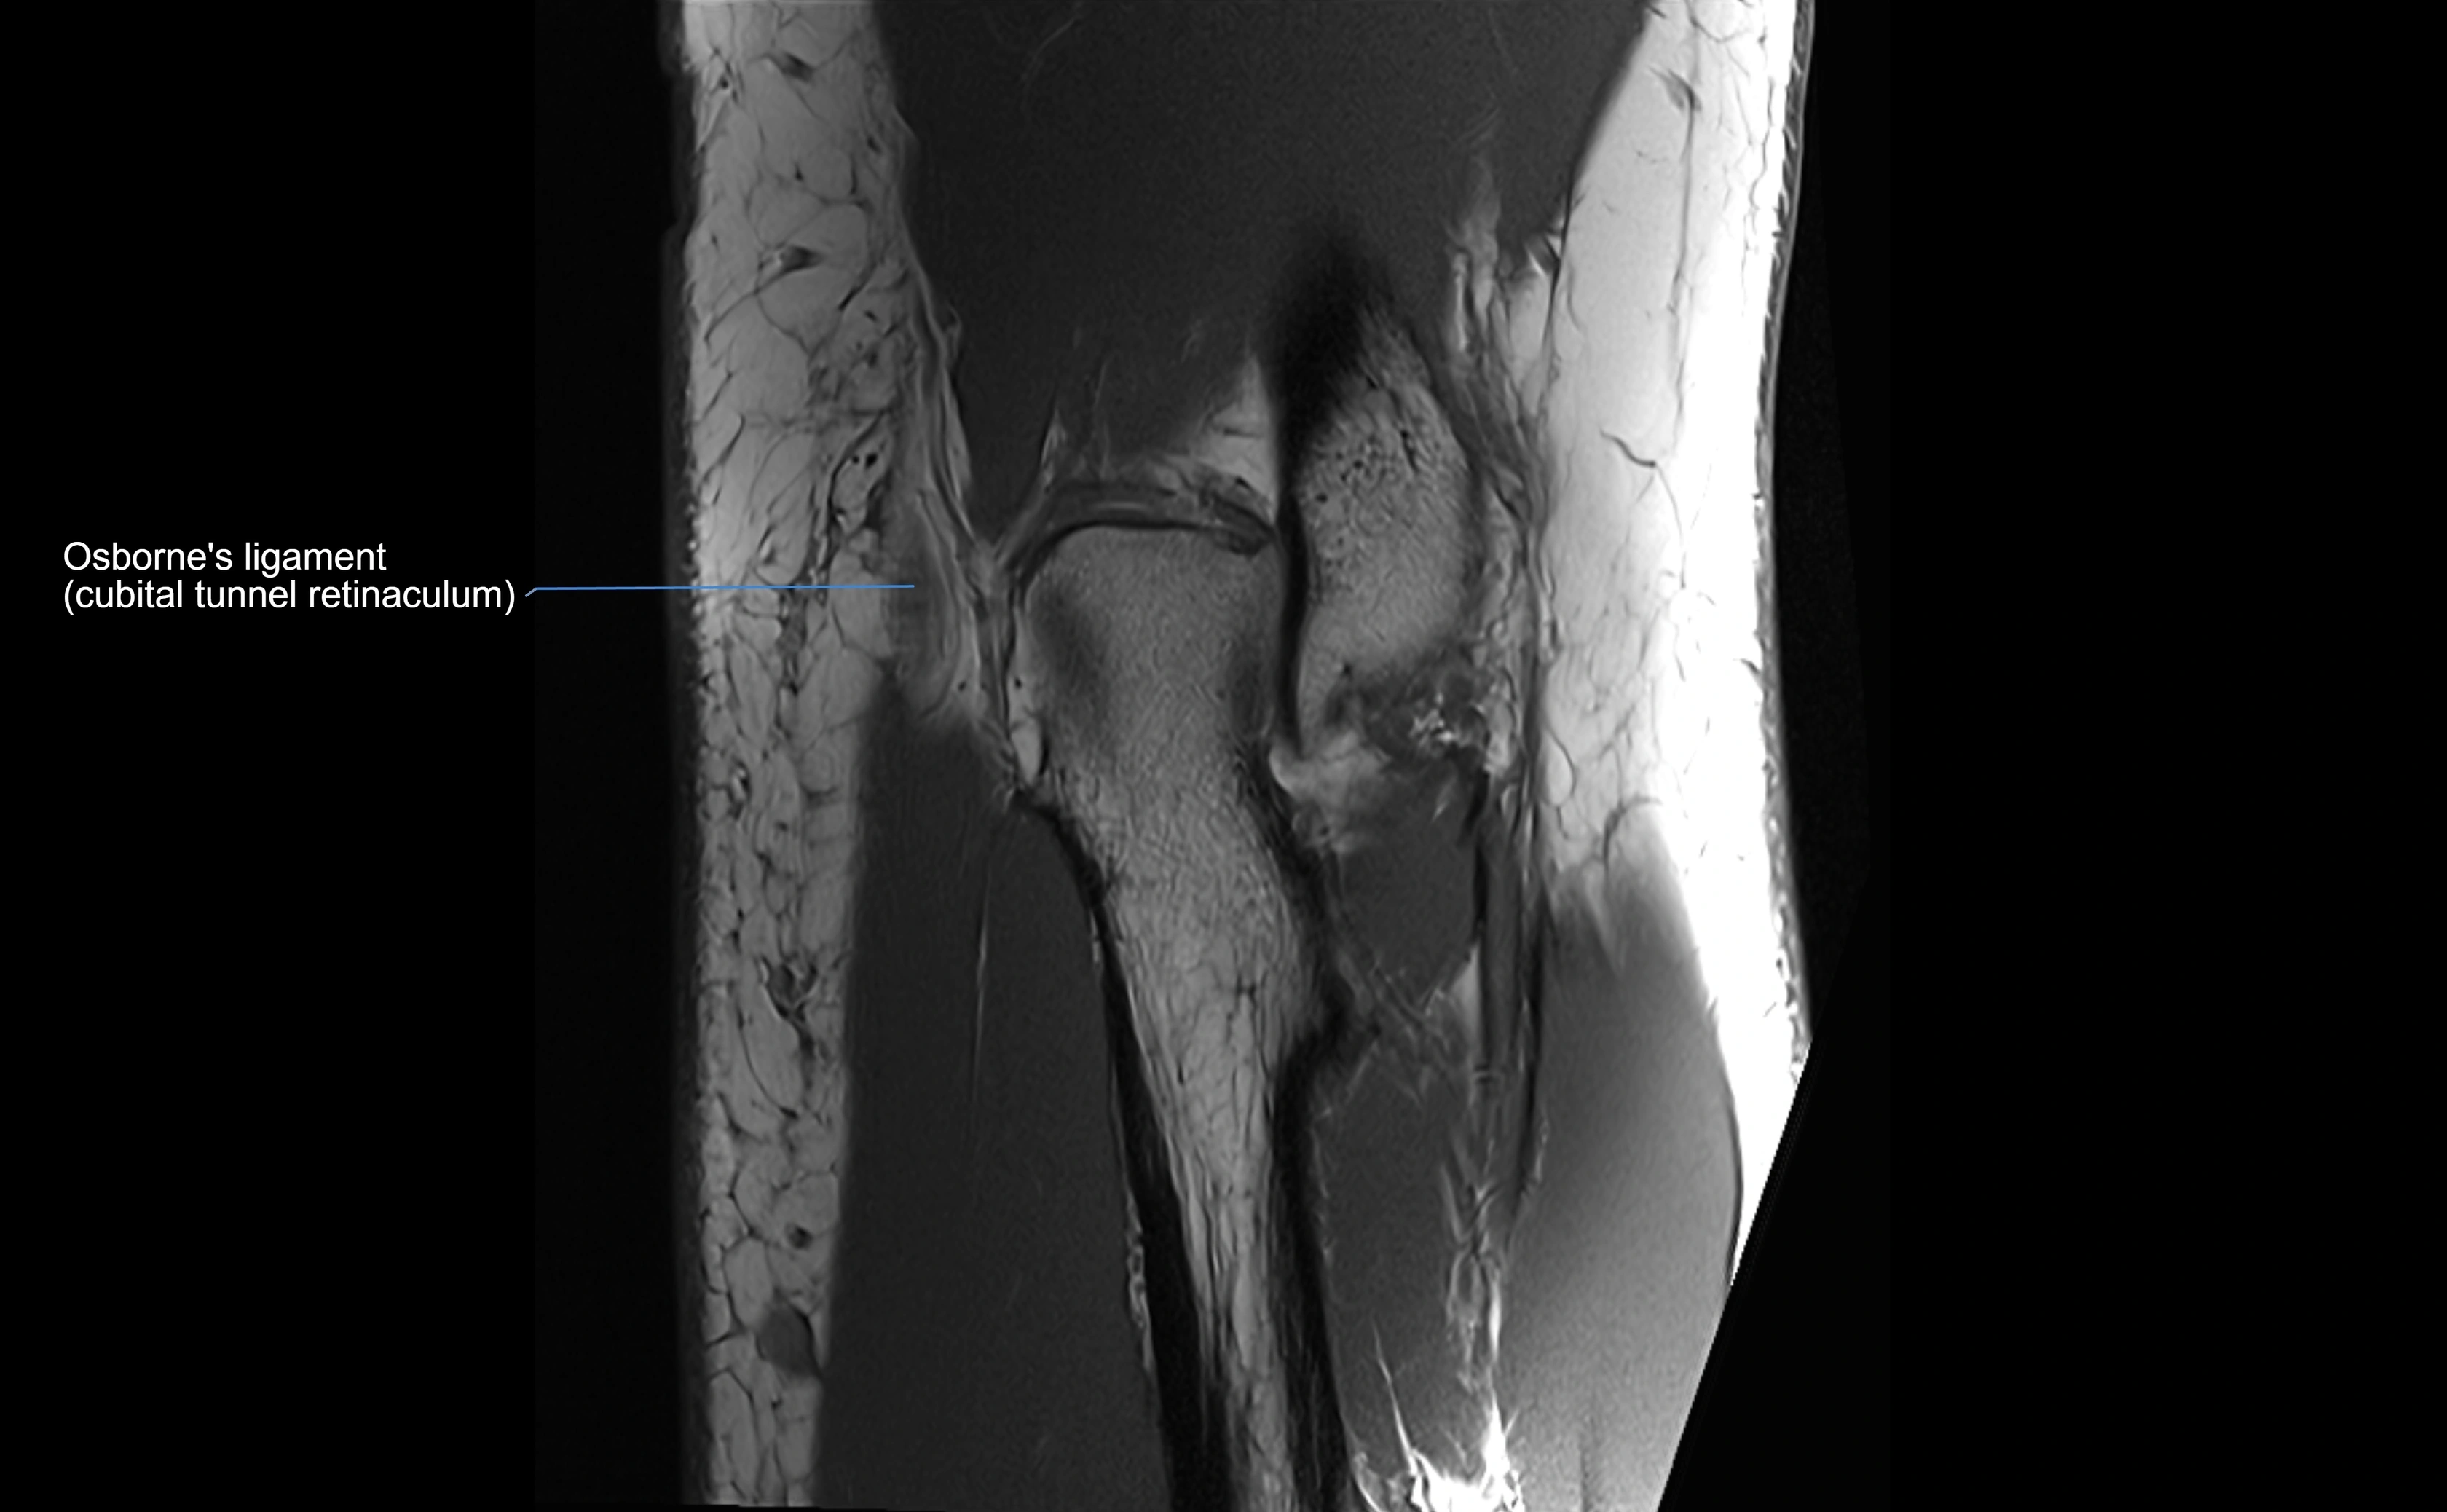

MRI Appearance

T1-weighted images:

• Ligament: low signal intensity (dark), appearing as a continuous band around the radial head.

• Adjacent fat and marrow: bright, creating contrast with the ligament.

• Thickening or disruption indicates injury or fibrosis.

• Joint capsule and synovium seen as thin low-signal lines contiguous with ligament margins.

T2-weighted images:

• Ligament: low signal (dark) with clear delineation from joint fluid.

• Fluid or edema: bright hyperintense, separating or surrounding the ligament in partial tears.

• Complete tear: discontinuity or non-visualization of ligament fibers, often with joint effusion.

MRI images

image